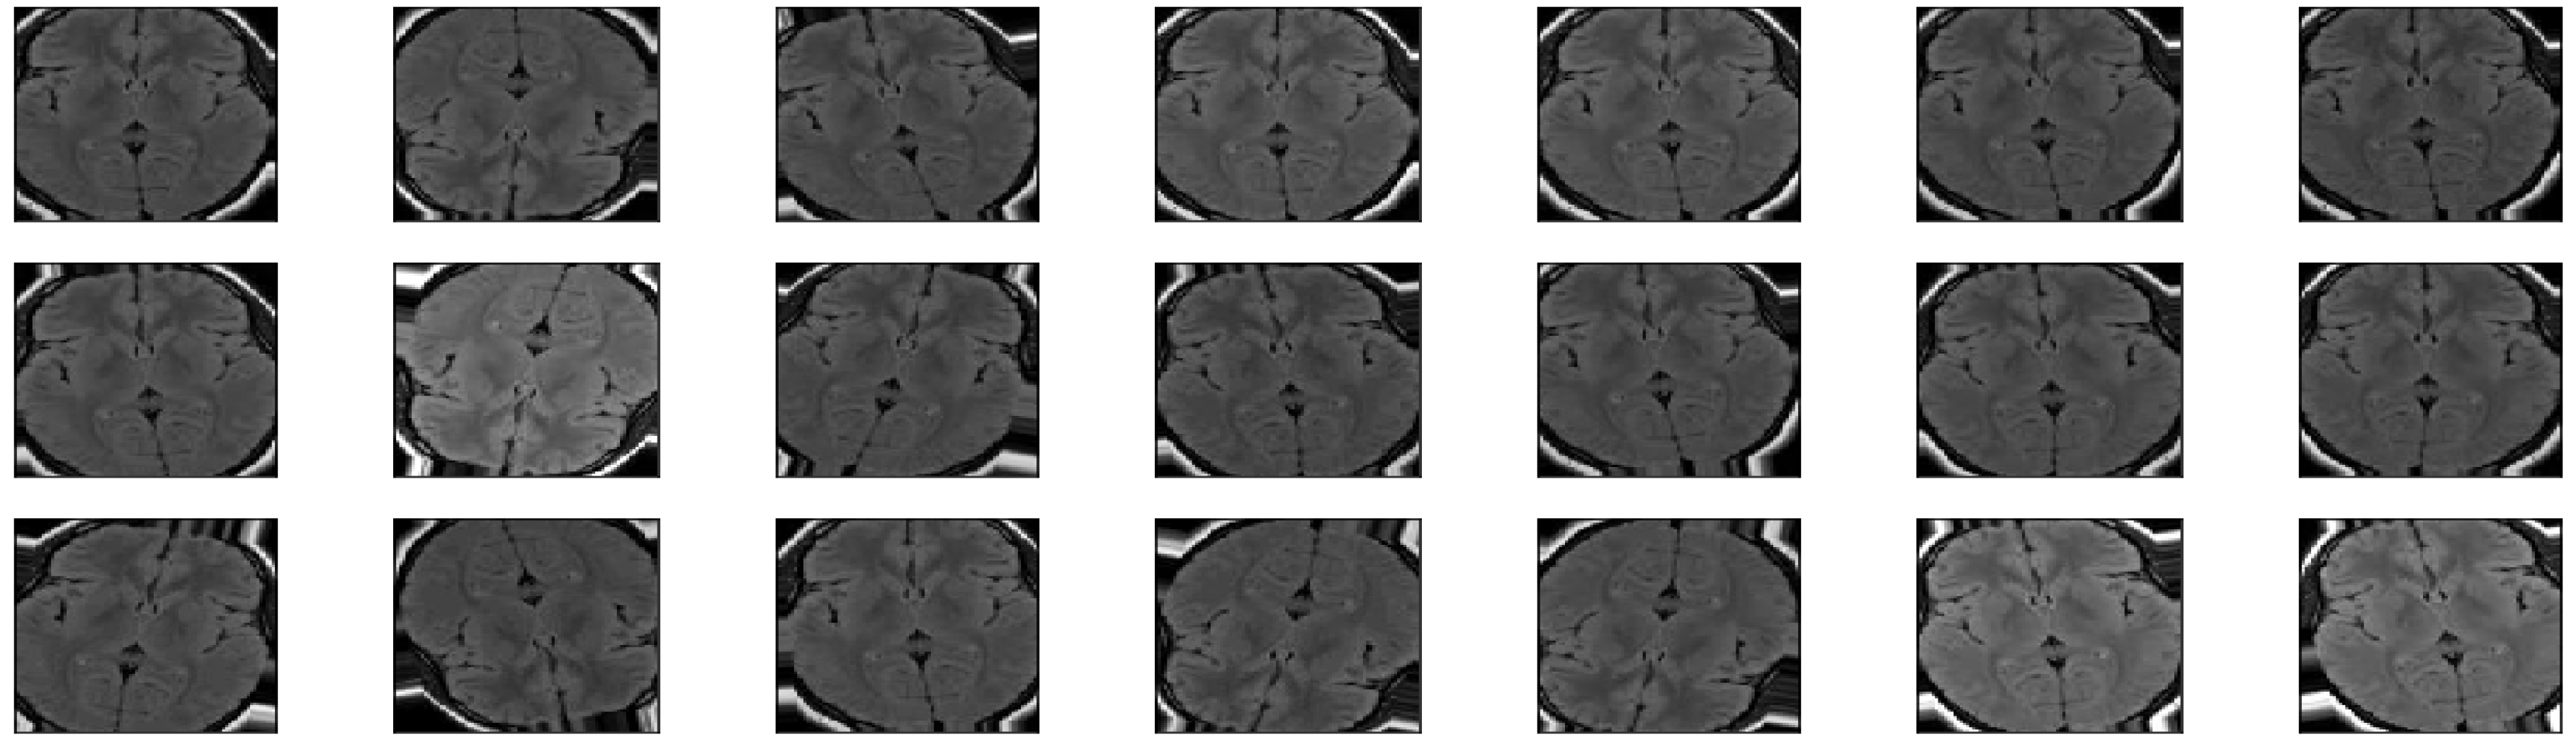

Once the model is trained, the best checkpoint is selected for model inferencing. The predicted classes are compared to the actual target classes to calculate the model accuracy, precision, recall and f-measure. Once the model has crossed the threshold accuracy of 90%, we try to understand the inner workings of the various layers of the model. Feature maps are generated for various input images. Feature maps help to determine the active areas of the image, i.e., The highlighted areas of the image that contribute to the classification decision. The activation maps for the various convolution and pooling layers are illustrated in Figure 4.

Figure 4.

Activation maps for various layers of the Dilated CNN. Each of the three convolutional layers depicts the granularity of the generated features with coarse features generated in Conv1 and fine features in Conv3. The MaxPooling layers reduce the resolution of the generated features using a kernel.

From the feature maps (Figure 4), we can deduce that the dilated CNN works on a well-described top-down approach. The outer layers (layer 1 and layer 2) focus on coarse features such as the shape of the brain or any problem areas (outliers–tumor locations). As we move through the layers, the granularity of the features decreases. The last layer generates features of fine granularity, and this means the focus is now on tiny sections of the image, that can determine small tumors. Finally, these generated feature maps are used to classify the MRI image using a Sigmoid activation function (binary classification).